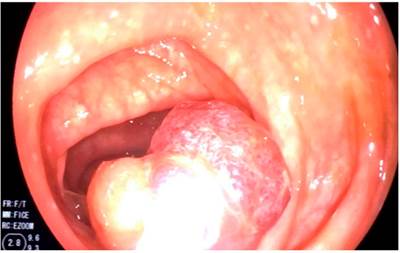

Durante la hospitalización, el paciente presentó una agudización de los síntomas, que se agravó por una rectorragia. Por este motivo, se solicitó realizar una colonoscopia total, en la cual se observó un gran pólipo pediculado de 40 mm, con un pedículo largo de aproximadamente 30 mm en el colon sigmoide, que mostró un prolapso causado por peristaltismo, lo que generó una obstrucción de la luz colónica (Figuras 1,2,3 y4). La cabeza del pólipo estaba erosionada como una probable causa de rectorragia.

Figura 1 Gran pólipo pediculado del colon.